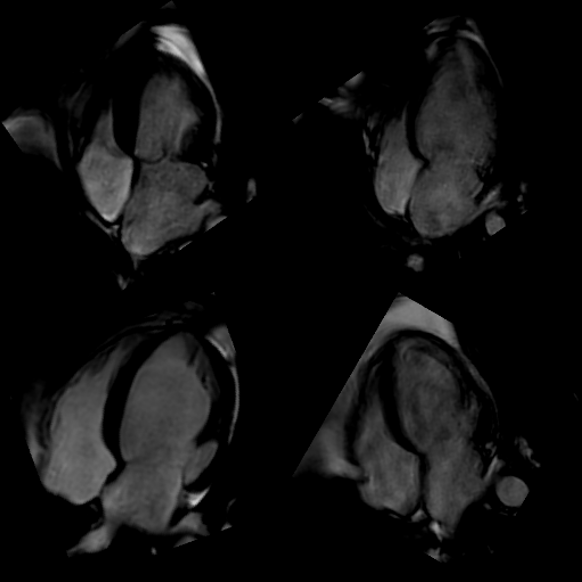

Figure 7: Initial cardiac MRIs are cropped to focus on the apical 4-chamber cardiac view and neighboring veins, then rotated to position the left ventricle in the upper left corner, aligning with the echocardiography view.

To compose the Echo2MRI dataset, we first extracted the regions containing the apical 4-chamber view from both echocardiogram and cardiac MRI videos. To simplify the learning, we aligned the cardiac MRI videos by rotating the cropped regions to roughly match the orientation of the echocardiograms, ensuring the left ventricle (LV) is positioned towards the top-right corner. Then, we extracted the frames containing 4-chamber cardiac views from these videos. Fig. 7 illustrates the pre-processing steps over the cardiac MRI frames.